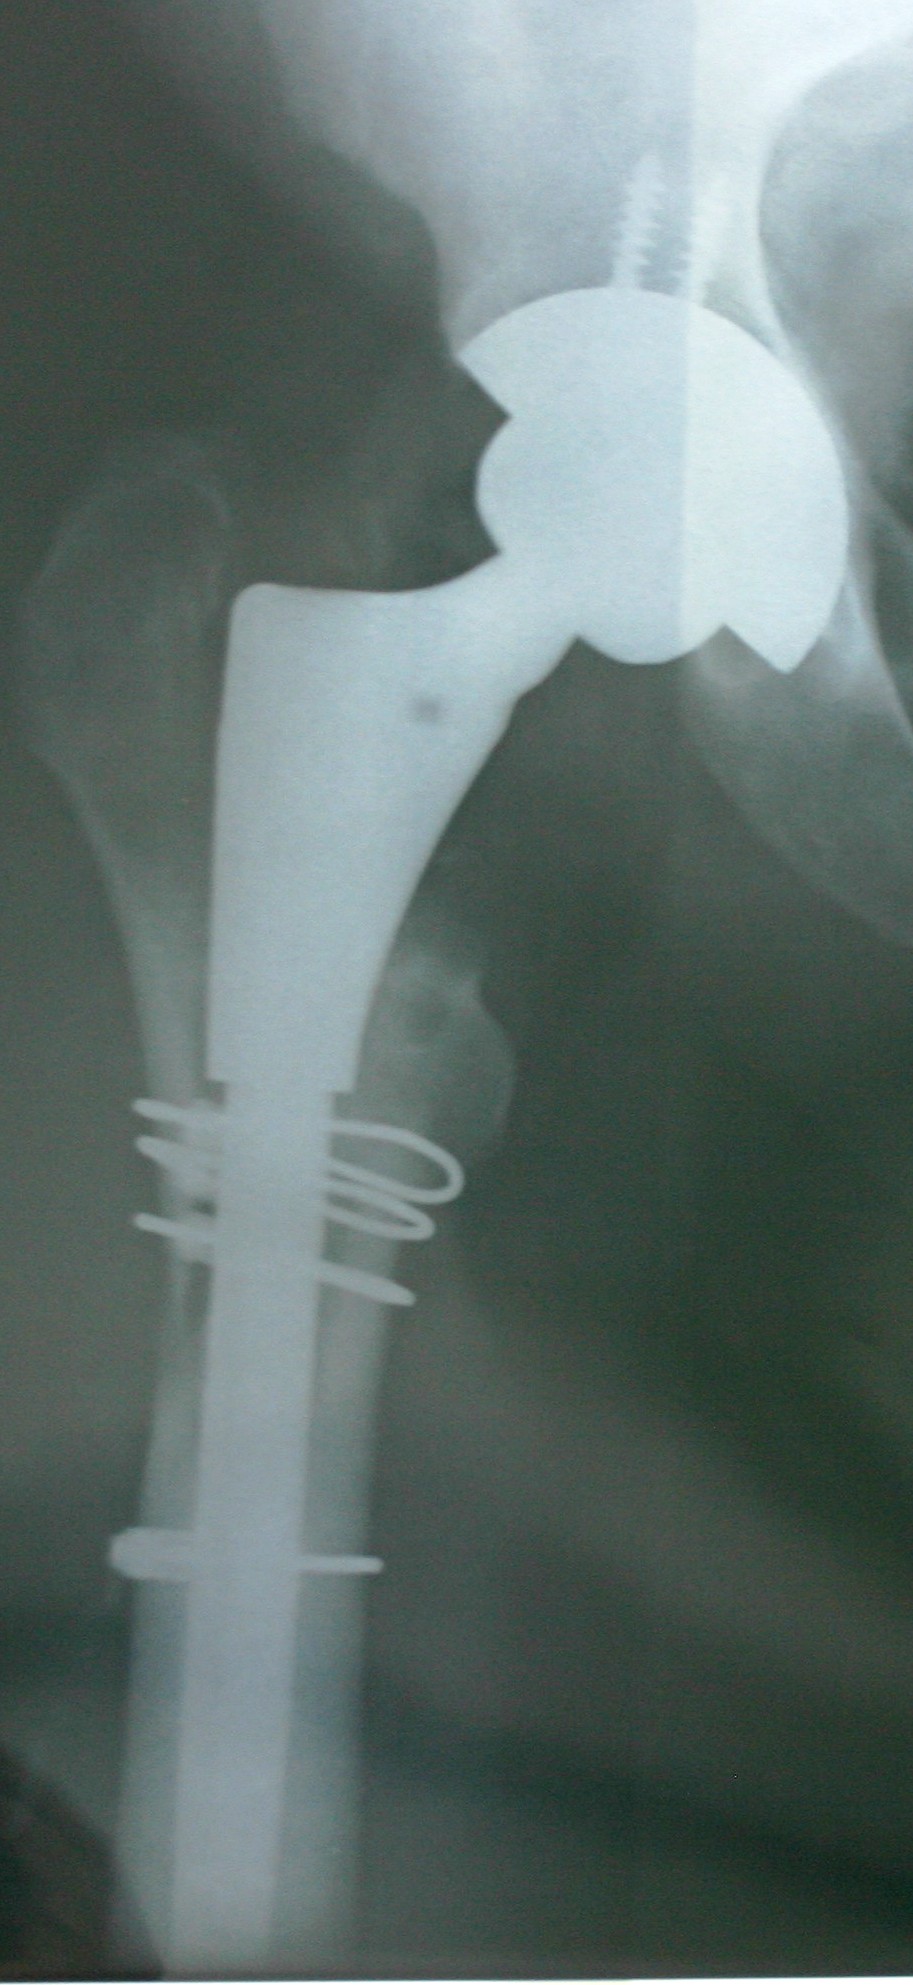

Here are the X-Rays of the revised hip – wired for everything except Digital FM, it seems!

- Split the femur to remove the previous Birmingham Spectron (S&N) femoral implant and remove excess glue and metallosis gunk.

- Bone graft to fill voids – wired femur back together to give bone strength while it heals – the fourth wire is to strengthen the mid femur because the new implant has a longer stem.

- New stem is press-fit.

- Then remove old acetabular cup – bone graft to fill out the void left – new cup put in and a couple of screws to make sure everything stays in place.

- Femoral head and cup are now inserted – ceramic on ceramic.

- The revision system is by Zimmer.

- To the right you can see the 38 or so stainless steel staples used to close the wound – removed on day 12 with only a few stings – no drama.

- The quality is not very good – taken on day one with me lying on a normal hospital bed and a very creative X-Ray team finding ways to get the required shots without moving me, the pain pump and the two drips too much – a real plumber’s muddle!

- Next week before I see the surgeon I will get a new set of X-Rays which should be a little crisper!